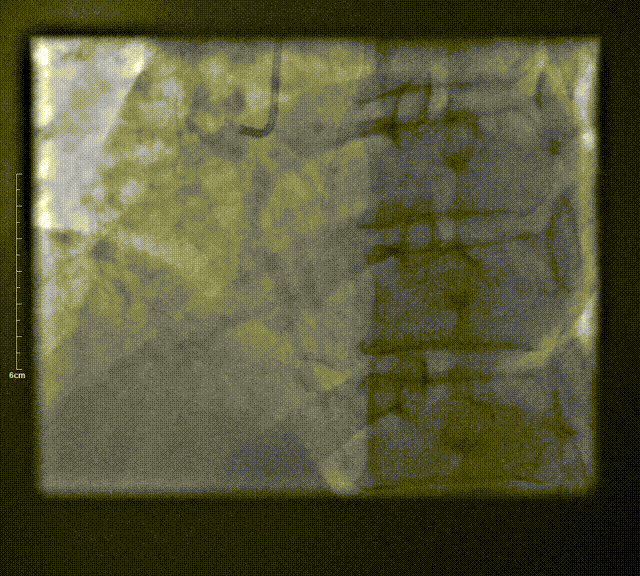

入院前检查(2025-01-14外院)行CAG术提示:左主干未见狭窄,前降支近中段后完全闭塞,前向血流TIMI 0级,回旋支近段60%-70%狭窄,远段95%狭窄,前向血流TIMI3级。右冠全程弥漫病变,近段至中远段,弥漫80%-90%狭窄,远段次全闭塞,前向血流TIMI3级,可见逆向血流供应前降支远段。